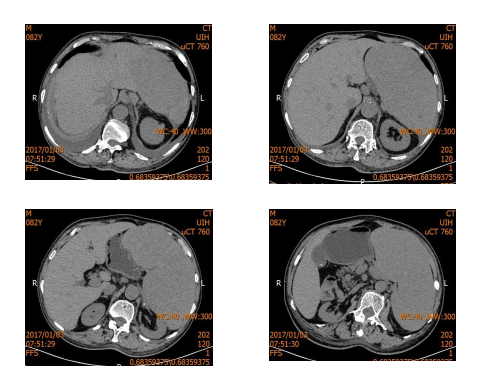

4.影像学检查

超声:脾肿大(厚 101 mm, 长径 202 mm),脾内高回声。

CT:脾肿大伴异常强化,副脾,肝脏及肾脏囊肿。

MRI:脾肿大伴多发异常信号,考虑脾脏淤血伴多发瘤样髓外造血可能,副脾,门脉、脾静脉明显增粗,肝脏、两肾囊肿。